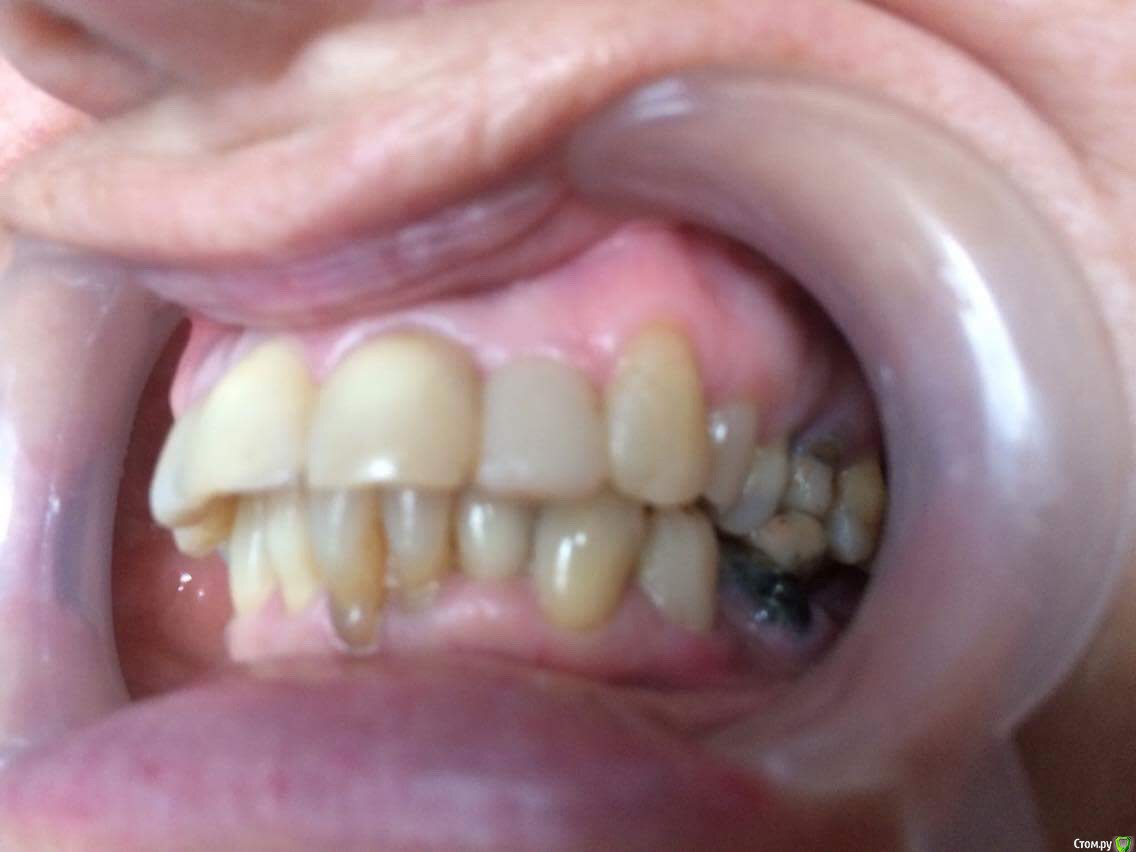

dr.Dre Опубликовано 27 июня, 2017 Поделиться Опубликовано 27 июня, 2017 Добрый день коллеги тему уже создавал но дал мало информации ,пациентка 58 лет .Помогите составить план лечения,имплантацию не потянет .Нужно ли здесь поднимать прикус? Ссылка на комментарий

chervoncevdaniil Опубликовано 27 июня, 2017 Поделиться Опубликовано 27 июня, 2017 (изменено) Док,фотопротокол вам мягко говоря подтянуть надо, боковые вообще не видно.Про имплантацию мы поняли,а остальное?Устраивает ли ее эстетика фронта,или просто хочет чтобы было чем жевать в боковом отделе?Как к съемному протезированию относится,потому что иначе вы 3 сегмент не закроете.Плюс вы же понимаете,что если вы прикус поднимете,то автоматически под коронки/виниры/накладки пойдут все зубы,включая интактный нижний фронт и витальные верх это вы с пациенткой обсудили? Может после этого уже и на имплантацию мотивация появится? Изменено 27 июня, 2017 пользователем chervoncevdaniil Ссылка на комментарий

dr.Dre Опубликовано 27 июня, 2017 Автор Поделиться Опубликовано 27 июня, 2017 Док,фотопротокол вам мягко говоря подтянуть надо, боковые вообще не видно.Про имплантацию мы поняли,а остальное?Устраивает ли ее эстетика фронта,или просто хочет чтобы было чем жевать в боковом отделе?Как к съемному протезированию относится,потому что иначе вы 3 сегмент не закроете.Плюс вы же понимаете,что если вы прикус поднимете,то автоматически под коронки/виниры/накладки пойдут все зубы,включая интактный нижний фронт и витальные верх это вы с пациенткой обсудили? Может после этого уже и на имплантацию мотивация появится?Эстетика не устраивает,пациент хочет все делать полностью ,к сьемному относиться отрицательно.Хочет ровные красивые зубы Ссылка на комментарий

chervoncevdaniil Опубликовано 27 июня, 2017 Поделиться Опубликовано 27 июня, 2017 (изменено) Ну в таком случае я не знаю как вы будете низ боковые сегменты протезировать,но 36 однозначно под удаление,26 и 27 в связи с деформацией плоскости видимо тоже придется,47 и 17 под вопросом и у нее получаются концевые дефекты.Опять же повторюсь,очень плохо видно что в боковом отделе,но настолько прикус вы навряд ли поднимете,чтобы и боковые зубы остались и при этом фронт не получился как у лошади,потому что по размерам резцы и клыки абсолютно нормальные Изменено 27 июня, 2017 пользователем chervoncevdaniil Ссылка на комментарий